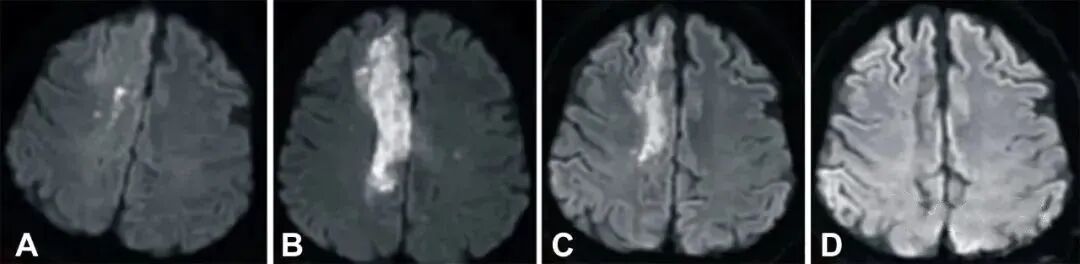

2019年,研究人员在《干细胞转化医学》(Stem Cells Translational Medicine)杂志上公布,干细胞有助于脑卒中偏瘫患者运动功能的恢复。9名年龄在30至65岁之间的偏瘫患者参与了这项临床研究,他们在中风后5-24个月接受干细胞脑内治疗,干细胞被注射至脑内梗塞灶附近。结果表明,干细胞治疗偏瘫性脑卒中拥有一定的临床益处。